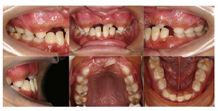

口内检查:全口口腔卫生较差。11、12、22、42未见萌出。

21部分萌出3~4 mm,牙龈缘稍红肿,与31反

,反覆

1~2 mm,反覆盖2 mm。

26、36釉质表面呈黄褐色,质硬、光滑,探及深窝沟,未探及龋坏。

55、16、65、46探及龋坏达牙本质中层,质软,无松动,叩诊(-),根尖区黏膜未见红肿、窦道等异常,扪诊无不适。

根尖片示:11自根中向远中弯曲约35°,属Ⅱ类弯曲牙,牙根发育至Nolla9期,21牙根发育至Nolla9期,腭侧见两颗正置锥形多生牙;12、22牙根发育至Nolla9期。

CBCT示:上颌恒牙胚萌出间隙不足,根据Moyers混合牙列分析法,牙弓现有长度为177.4 mm,牙弓应用长度为181.6 mm,拥挤度为4.2 mm。42缺失;11、21、22发育至Nolla9期;55、16、65、46冠部低密度影及牙本质中层,根管内未见高密度充填影,根尖周未见明显异常。53、63牙根吸收不足1/3,13、23发育至Nolla8期。